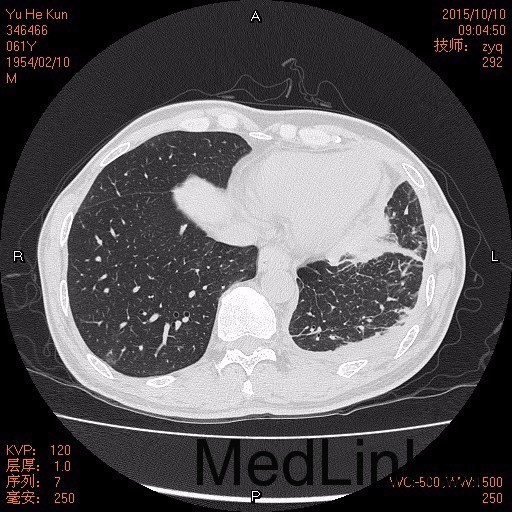

查体: T 36.8℃,BP 100/61mmHg,胸部可见既往胸腔镜检查愈合疤痕,双肺呼吸音清,双下肺呼吸音粗,未闻及干湿性罗音。 辅查: 1.胸膜活检:病变符合胸膜慢性炎伴间皮细胞增生。 2.胸水离心找癌细胞:见增生的间皮细胞,淋巴细胞,未见癌细胞 3.胸部,上腹部CT:胸膜间皮瘤”治疗后复查,1.双侧胸膜增厚较前增多、明显,左肺癌性淋巴管炎,纵隔多发淋巴结转移可能。2.左侧少量积液较前减少,现片示少量包裹性液-气胸,左肺下叶节段性压迫性肺不张。3.少量心包积液。4.符合贫血改变。